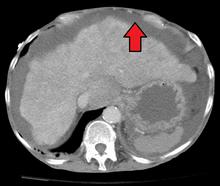

那时患者总觉得人特别累、腹胀、食欲不振。住院过程中,发现腹水:按照肝病的理论,出现腹水的慢性肝病,结合B超检查,考虑肝硬化失代偿期。

肝硬化腹水

肝硬化腹水的B超影像表现